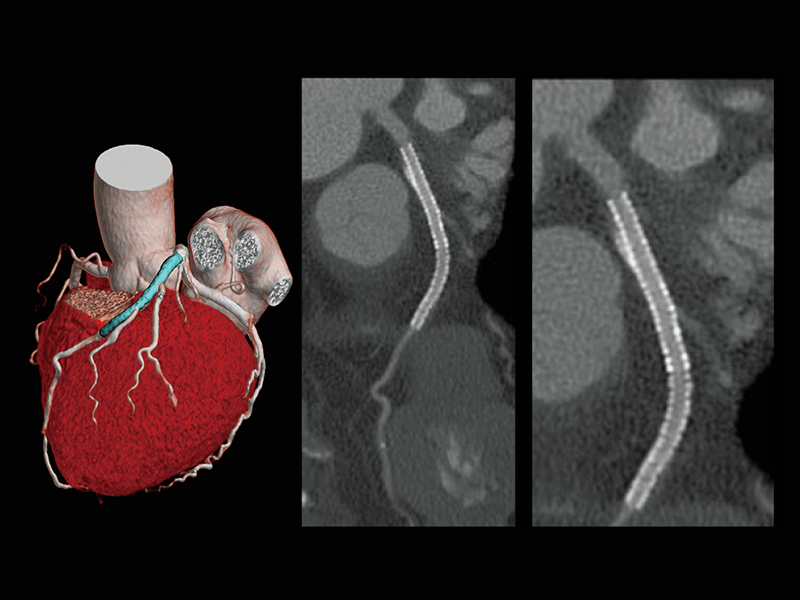

Follow-up after CABG

Follow-up after LAD stenting

- * Images other than axia images were processed by the 3D image analysis system SYNAPSE 3D.